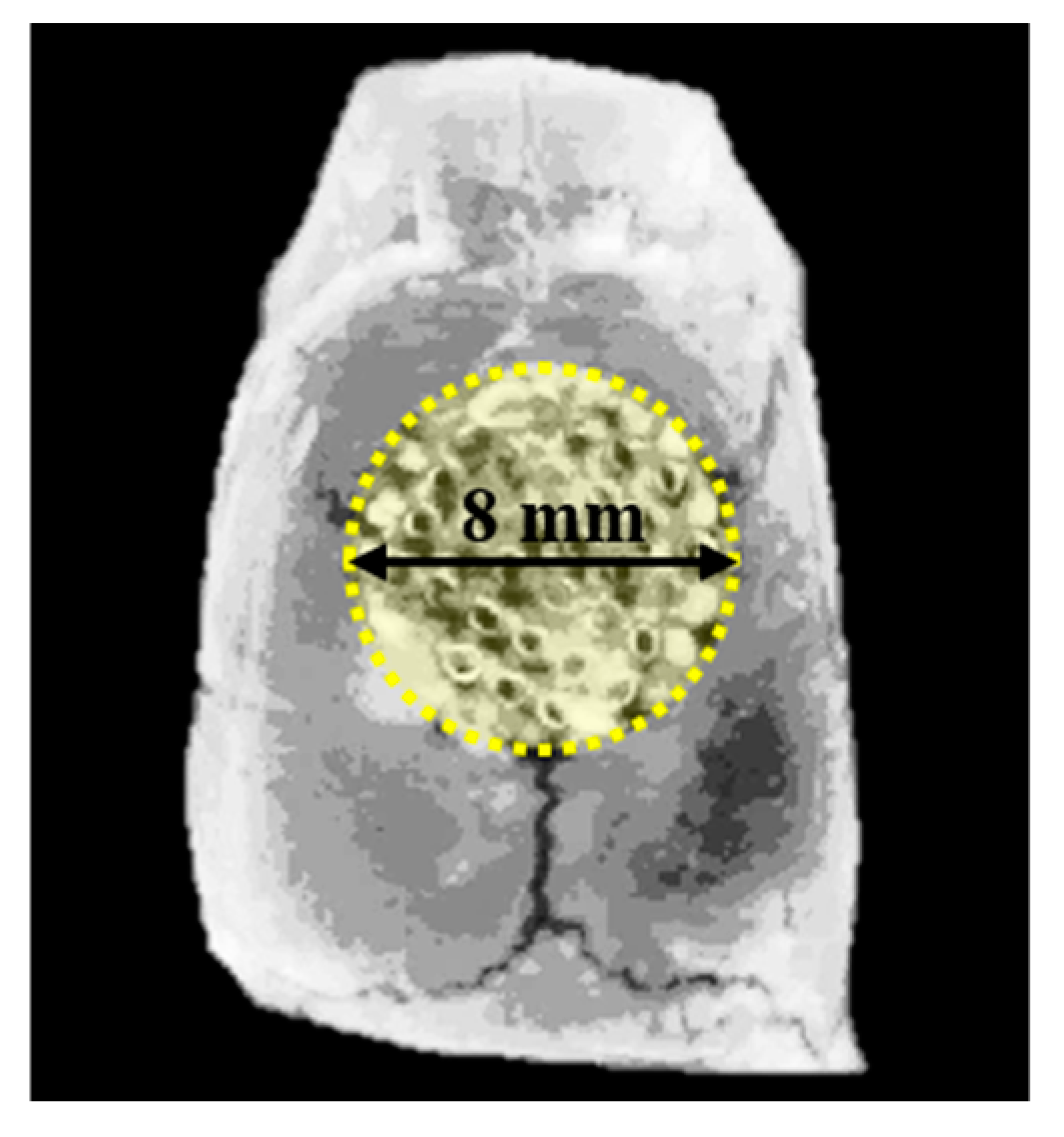

2.3.3. Micro-Computed Tomography (μCT) Analysis

2.3.4. Histologic and Histometric Procedures